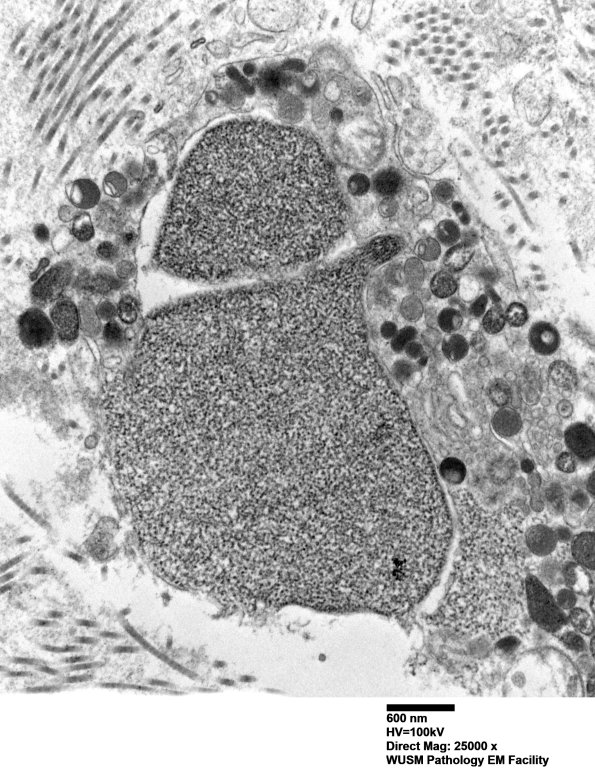

Within collagenous areas swollen structures were encountered which consist of autophagic vacuoles and tubulovesicular elements. We think these are swollen regenerative structures similar to axonal growth cones, likely by deviation into an area not conducive to regeneration. (electron micrographs)